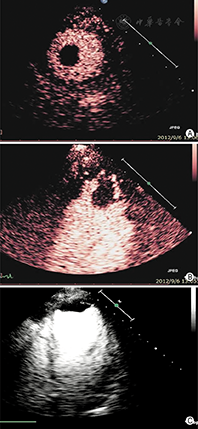

②左心室心尖肥厚:7%肥厚型心肌病为心尖明显肥厚。常规超声心动图检查因不能完整清晰显示心尖,将使15%心尖肥厚型心肌病漏诊。当怀疑是心尖肥厚型心肌病而不能被明确或排除时,应该进行心脏造影检查(图4)。心尖肥厚型心肌病左心室心腔轮廓的典型造影表现为左心室腔呈"铲子样" (spade-like)的外观,心尖部室壁明显增厚(图5);在心尖肥厚型心肌病中肥厚的心尖部造影剂灌注通常是相对减少的,与心腔内的高强度造影剂形成明显的对比[25]。

③左心室心肌致密化不全:心肌致密化不全是一种罕见的、但是越来越多地被临床认识的疾病,可导致心力衰竭、心律失常、血栓栓塞事件和死亡。室壁由增厚的运动减弱的两层心肌组成:较薄的致密化心外膜下心肌和较厚的非致密化心内膜下心肌。当怀疑左心室致密化不全,但传统的二维超声成像不能清晰显示窦隙状非致密化心肌时,造影超声心动图检查可显示突入左心室腔肌小梁之间的血池内有造影剂填充[26,27,28](图6,图7)。采用MI 0.3~0.5谐波成像,有助于更清楚显示肌小梁间隐窝。目前,孤立性左心致密化不全的诊断标准尚未统一,但通过超声造影显示非致密化心肌厚度与致密化心肌厚度比值> 2时有助于该病的确诊。